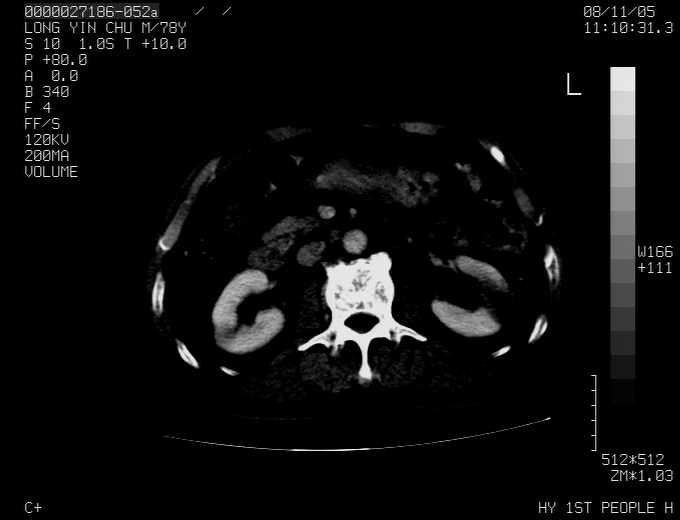

标题: CT16532:M78Y,肝脏病变,请会诊

腹胀,腹痛就诊,男性,78岁,外院b超未见异常。

考虑弥漫性肝癌并脾及双肾转移.双侧胸水.

肝脾肾转移瘤可能性大,左肾不除外梗塞,双侧胸水

考虑肝癌并双肾及脾脏转移;双侧胸腔积液。